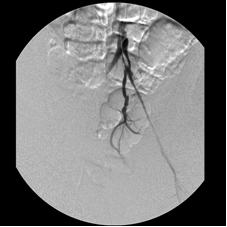

This 41-year-old woman smoked for a long time and developed severe bilateral calf cramping after short walks. Investigation revealed that she had completely occluded her distal abdominal aorta and her right and left iliac arteries, severely restricting the flow of blood into her lower limbs. She was unwilling to have surgery and came to me for minimally invasive treatment. By dripping urokinase (a clot dissolver) over 72 hours through two catheters that I advanced across the occlusions and later stenting the opened arteries, I wholly restored blood flow through her iliac channels. She walked again – without cramps.